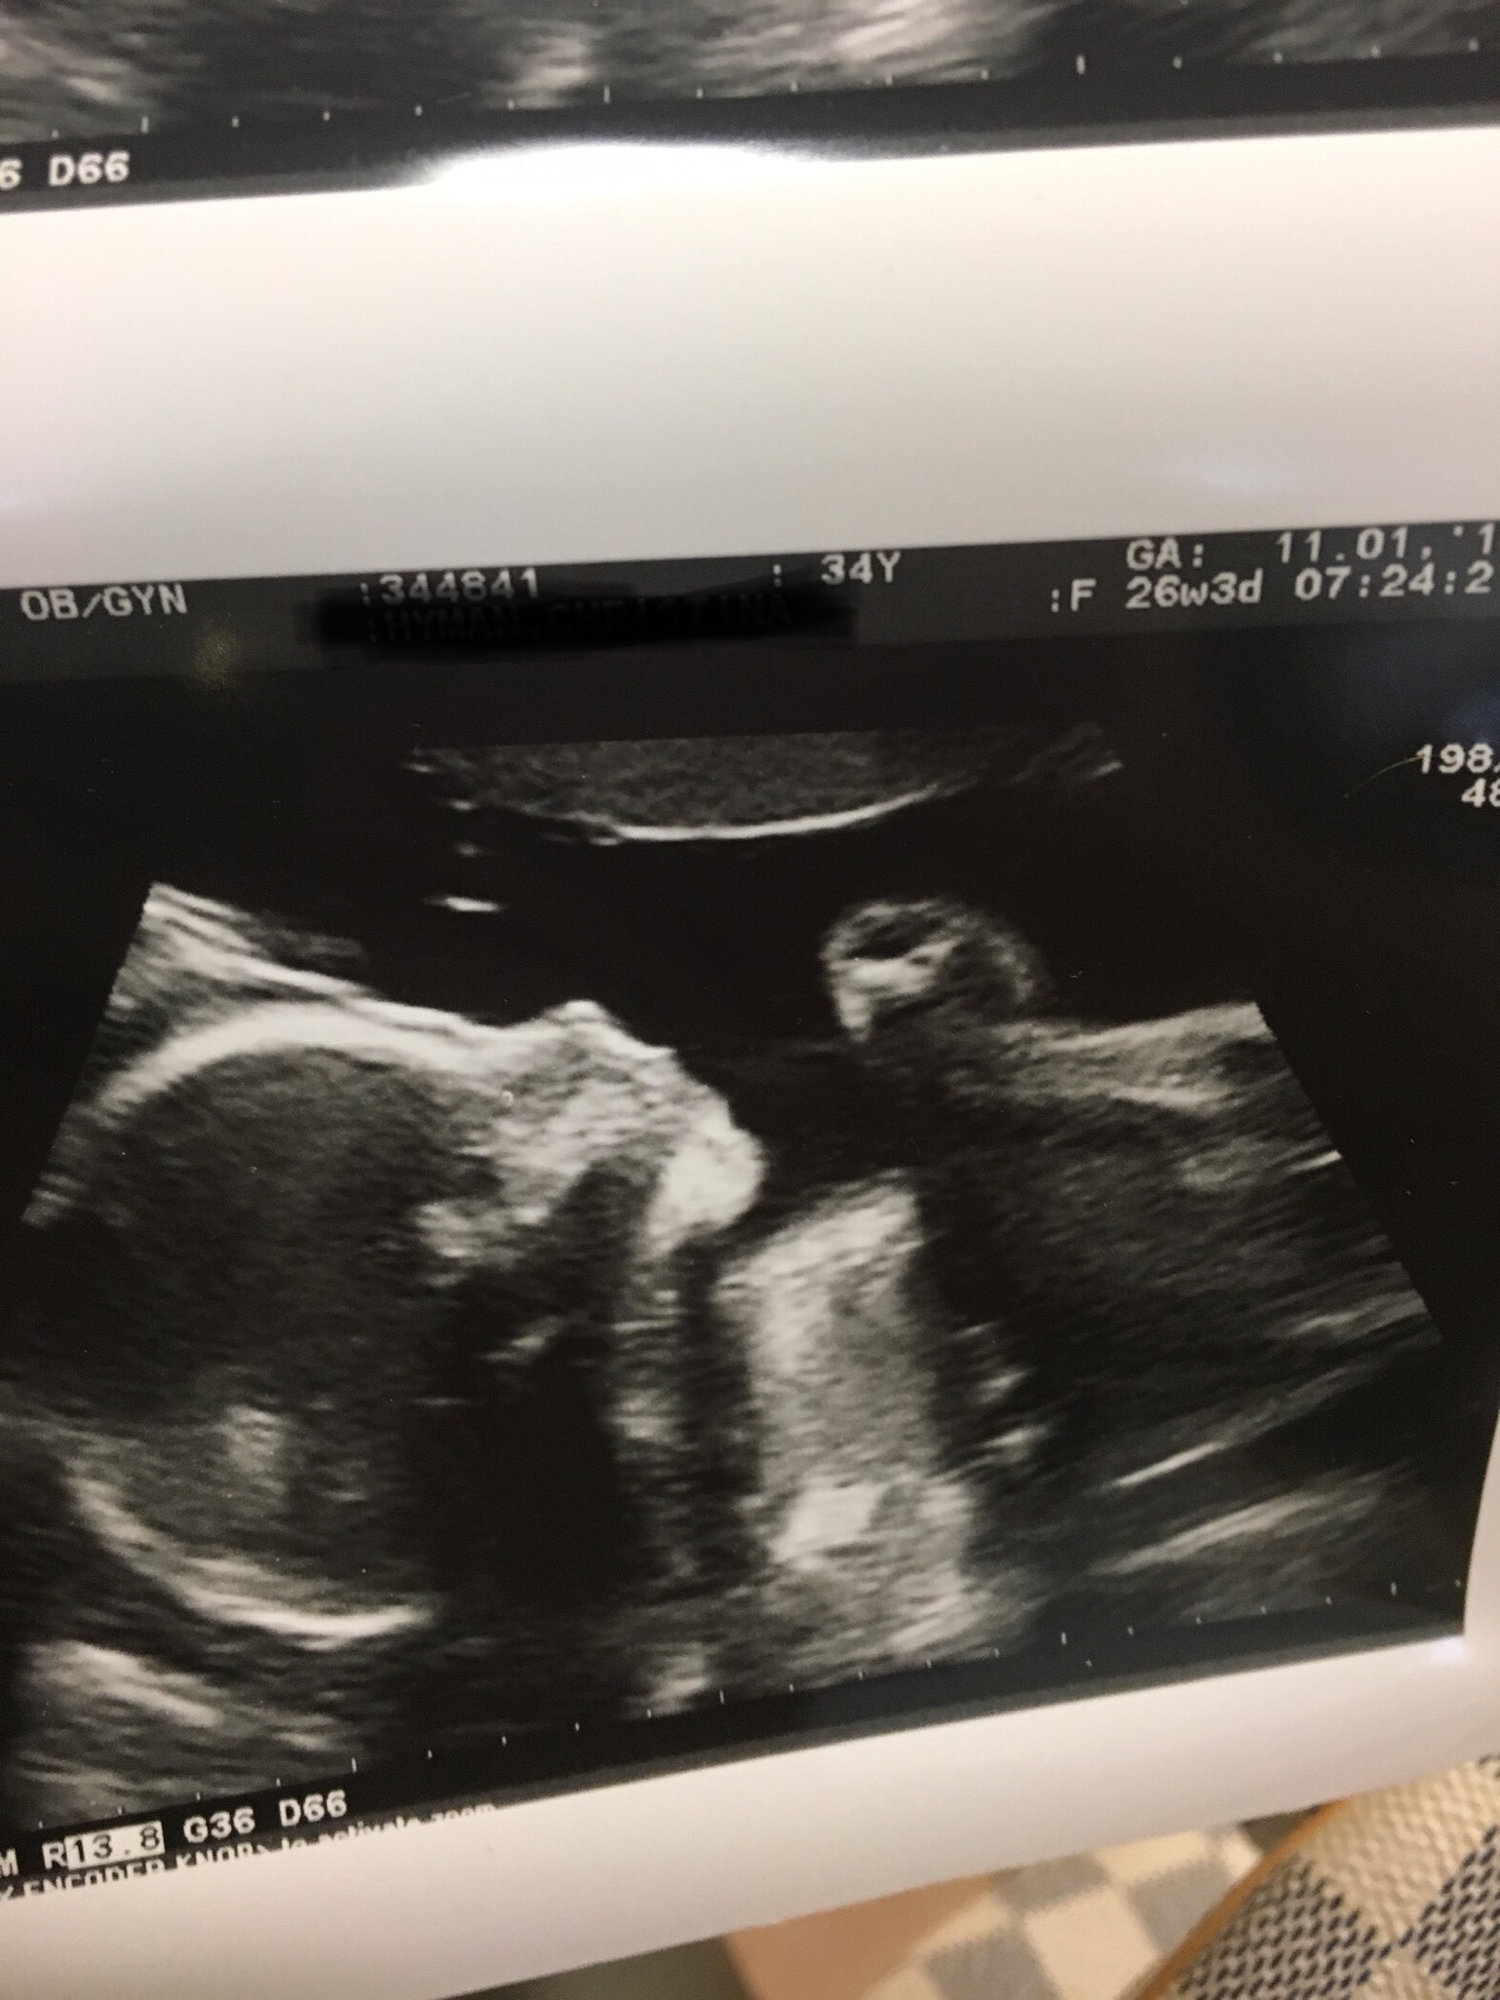

Ultrasound went great!! Baby boy is measuring to the day (26 weeks 3 days), 1 lb 15oz, NORMAL HEARTBEAT!! and frank breech (butt down, head/feet up) which doctor isn’t worried about until 36 weeks. But I had already told my H that this baby will most likely be breech with how he’s been keeping us on our toes haha. I get another ultrasound in a month to check on things.

ETA a pic of the cute little stinker.